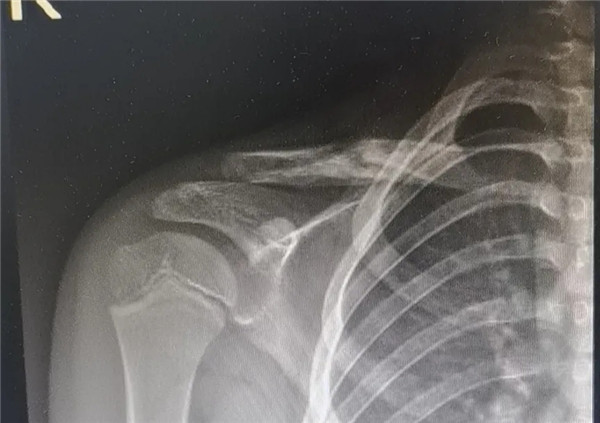

复位前

经拍片显示,洋洋右锁骨中远段骨折。查体时,洋洋右肩部肿胀,有压痛感,右肩关节上举、外展活动受限,建议其入院并接受手术治疗。洋洋妈妈当即办理了入院手续。

6月3日,在征得家属同意,洋洋的身体符合手术指征后,洋洋接受了右锁骨骨折切开复位内固定术,手术由应文世主任主刀。术中可见右锁骨呈粉碎性骨折,骨折端移位明显。一个小时后,手术顺利结束。术后,洋洋恢复良好,6月9日顺利出院。一个月后,在来复查时,洋洋的妈妈带来了一面锦旗送予应文世主任及手外科周小君副主任,以感谢他们的高超技术及优质服务。

复位后